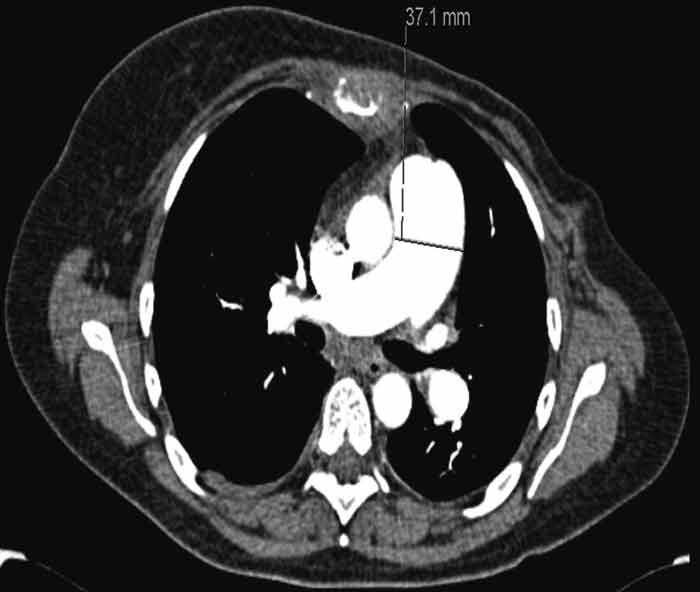

CT thorax on the 16th day from admission showed a further expanded truncus pulmonalis, 37 mm (fig. 2) and newly developed scattered, consolidating opacities in the upper lobe of the left lung. Compared with previous ECGs, a new ECG showed findings as with right-side strain and a QR pattern in V₁, negative T in V₂ and pronounced R-loss in the anterior wall leads. The patient was referred for echocardiography, which was planned for the next day. From the same day she had increasing tachycardia and hypotension and after a while was transferred to the Pulmonary Ward's observation department for BiPAP respiratory support. On the morning of the 18th day since admission (about ten weeks after the very first hospitalisation for dyspnoea) the patient suddenly suffered respiratory arrest and was unresponsive. Advanced heart-lung resuscitation was initiated, but it was not possible to re-establish independent circulation. The patient was declared dead about 30 minutes after the start of resuscitation.

Figure 1  Volume CT thorax with intravenous contrast taken during the first admission to hospital. The truncus pulmonalis…

Figure 1 Volume CT thorax with intravenous contrast taken during the first admission to hospital. The truncus pulmonalis has normal dimensions

Figure 2  Volume CT thorax with intravenous contrast taken during last hospitalisations shows pronounced truncus pulmonalis…

Figure 2 Volume CT thorax with intravenous contrast taken during last hospitalisations shows pronounced truncus pulmonalis with diameter 37 mm causing suspicion of pulmonary hypertension